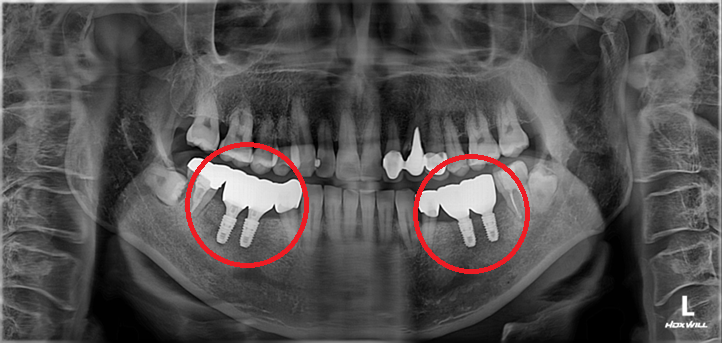

양쪽 어금니 임플란트 치료 #2

작성자